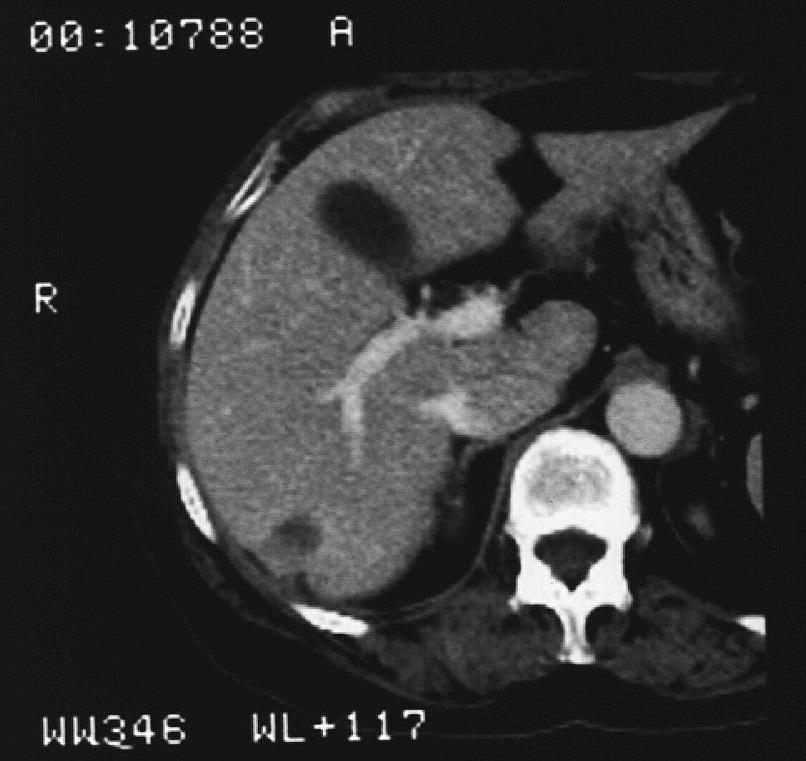

- Hemorrhage (subcapsular (figure 12.), parenchymal, intraabdominal (figure 13.), intrathoracic, pseudoaneurysm),

Image

Figure 12. – US guided renal biopsy, subcapsular hemorrhage (5 minute control)